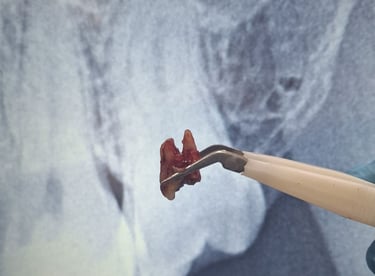

Teeth Extraction

After

Before

All images shown here represent real clinical cases of teeth extractions done at our dental clinic with patient consent.

Tooth extraction is performed when a tooth is severely damaged, infected, or cannot be saved through other dental treatments. At Shree Dental Care, we carry out tooth extractions using gentle techniques to ensure minimal discomfort and faster healing.

Patients from Shyamal and nearby areas of Ahmedabad visit our clinic for comfortable teeth extractions carried out using modern techniques and strict hygiene protocols.

At Shree Dental Care, we ensure:

Thorough clinical examination and digital X-rays.

Gentle and painless extraction techniques.

Proper anesthesia for patient comfort.

Post-extraction care instructions for fast healing.

Our goal is to make the procedure as smooth and stress-free as possible.